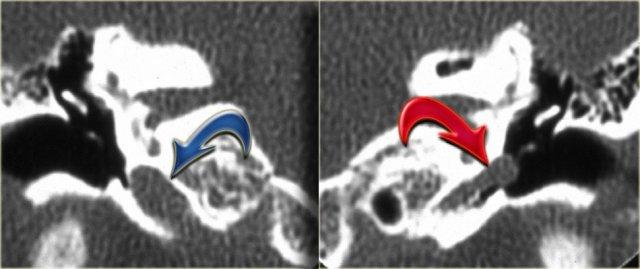

Bên trái là các ảnh cắt coronal của cùng một bệnh nhân.

Bên phải, động mạch cảnh trong tách biệt hoàn toàn với tai giữa (mũi tên xanh dương).

Bên trái, động mạch cảnh trong đi xuyên qua tai giữa (mũi tên đỏ).